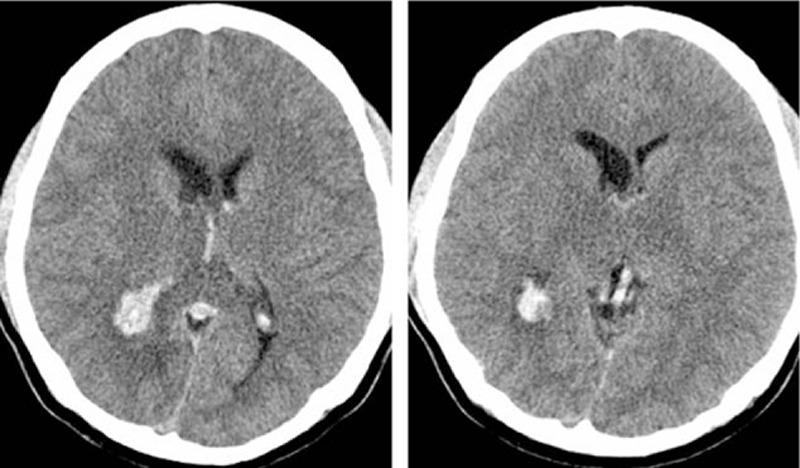

Intraventricular hemorrhage (IVH) may occur as an isolated event from primary ventricular bleeding or as a complication of brain hemorrhage from another etiology. It is associated with high mortality and morbidity. The underlying risk factors include hypertension and aneurysms, among others. However, not all the exact etiologies are known. In this study, a case of a 24-year-old man who suffered from a headache and a decline in memory has been reported. A brain computed tomography scan suggested the diagnosis of spontaneous intraventricular hemorrhage. However, brain magnetic resonance imaging, magnetic resonance venography, and other tests eventually confirmed cerebral venous sinus thrombosis.Cerebral venous sinus thrombosis may be one of the causes of intraventricular hemorrhage and should be considered for unexplained intraventricular hemorrhage.

脑室内出血(IVH)可能是原发性脑室出血的孤立事件,也可能是其他病因导致脑出血的并发症。它与高死亡率和高发病率相关。潜在风险因素包括高血压和动脉瘤等。然而,并非所有确切病因都已知。在本研究中,报告了一例24岁男性,他出现头痛和记忆力减退。脑部计算机断层扫描提示自发性脑室内出血的诊断。然而,脑部磁共振成像、磁共振静脉造影及其他检查最终确诊为脑静脉窦血栓形成。脑静脉窦血栓形成可能是脑室内出血的原因之一,对于不明原因的脑室内出血应予以考虑。